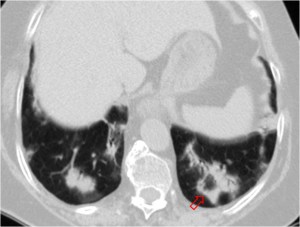

Esta segunda imagen corresponde a ascitis. Observa como la interfase entre el bazo y el líquido (flecha) es más nítida que en la imagen anterior. También lo es la interfase entre el hígado y el líquido.

SIGNO DEL ÁREA DESNUDA

Cuando en la TC vemos líquido en situación dorsal al hígado (flecha), éste se encuentra en la cavidad pleural, ya que el líquido intraperitoneal no puede acumularse en esta zona debido a que el peritoneo se repliega sobre la cúpula hepática sin llegar a cubrir la parte posterior del hígado, es decir, que no hay cavidad peritoneal por detrás del hígado y, por tanto, la ascitis no puede ocupar este espacio.

En esta imagen también está presente, lógicamente, el Signo de la interfase.